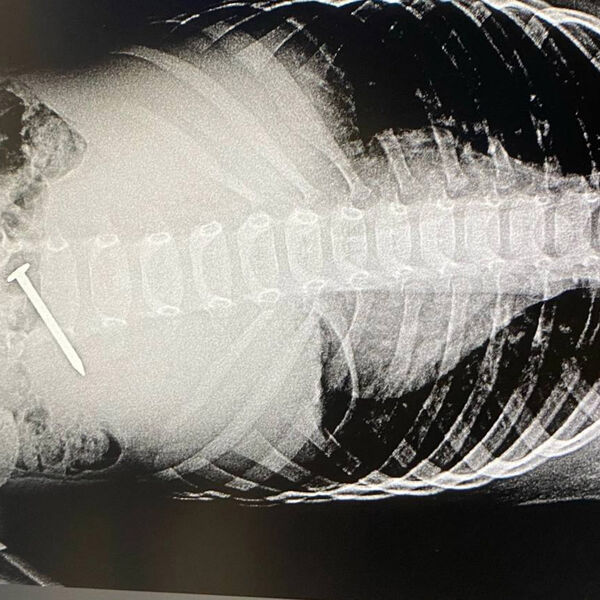

Российские врачи спасли трехлетнего ребенка, проглотившего гвоздь

В Татарстане трехлетний ребенок проглотил пятисантиметровый гвоздь

Врачи Альметьевской детской городской больницы спасли трехлетнего мальчика, который проглотил гвоздь. Об этом сообщили в пресс-службе медицинского учреждения.

Ребенок проглотил гвоздь во время игры, о чем позже рассказал матери. При этом инородный предмет пациента не беспокоил.

Мальчику провели диагностику, которая показала, что гвоздь расположился поперек двенадцатиперстной кишки.

«Гвоздь встал поперек, и можно было повредить стенку кишки, врачам удалось «стащить» инородное тело в желудок, что технически очень тяжело. Из желудка гвоздь извлекли корзинкой Дормиа (медицинский инструмент, предназначенный для захвата — «Газета.Ru»)», — поделились в пресс-службе больницы.

Четверо суток педиатры наблюдали за состоянием пациента и после контрольного обследования отпустили его домой.